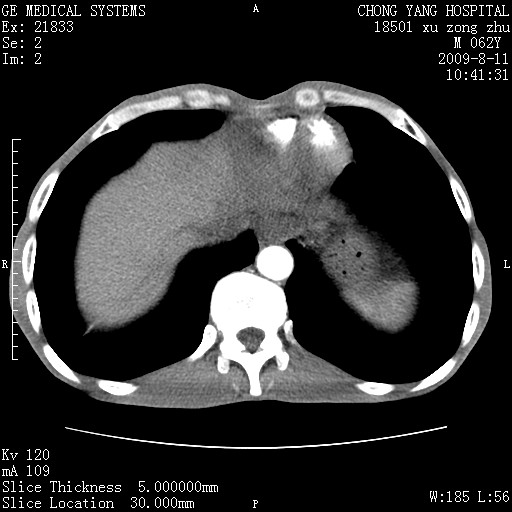

以下是引用杀毒软件在2009-8-11 16:35:00的发言:[br]肝内胆管扩张局限于左叶,胆管内有结石伴肝外胆管结石,胆管壁增厚呈弥漫性并发腹腔积液,胰腺边界模糊。[br][br]考虑---胆总管及肝内胆管结石继发胆管炎及胰腺炎,左肾下极囊肿,腹水。

以下是引用zjzjr在2009-8-11 17:35:00的发言:[br]肝内胆管扩张局限于左叶,胆管内有结石伴肝外胆管结石,胆管壁增厚呈弥漫性并发腹腔积液。[br][br]考虑---胆总管及肝内胆管结石继发胆管炎,左肾下极囊肿,腹水。